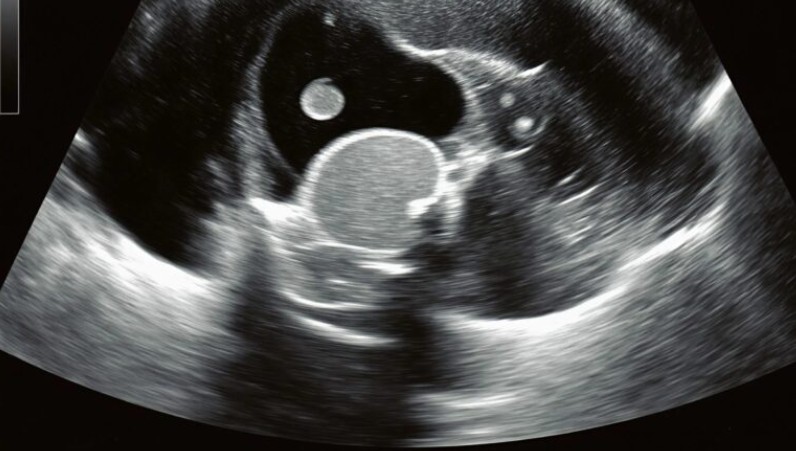

Acil servis koridorlarında zaman buz kesti. Kızım sedyede acı içinde kıvranırken doktorların endişeli bakışları altında ultrason sonuçlarını bekledik. Sonunda doktor yanımıza gelip o hiçbir ebeveynin duymak istemediği cümleyi kurdu: “Acil ameliyat gerekiyor.” Meğer o sırt ağrıları sandığımız gibi çantadan değil, sessizce büyüyen bir böbrek taşından kaynaklanıyormuş. Taş yerinden oynayıp kanala düştüğü için şiddetli sancı ve hayati risk oluşturmaya başlamıştı.